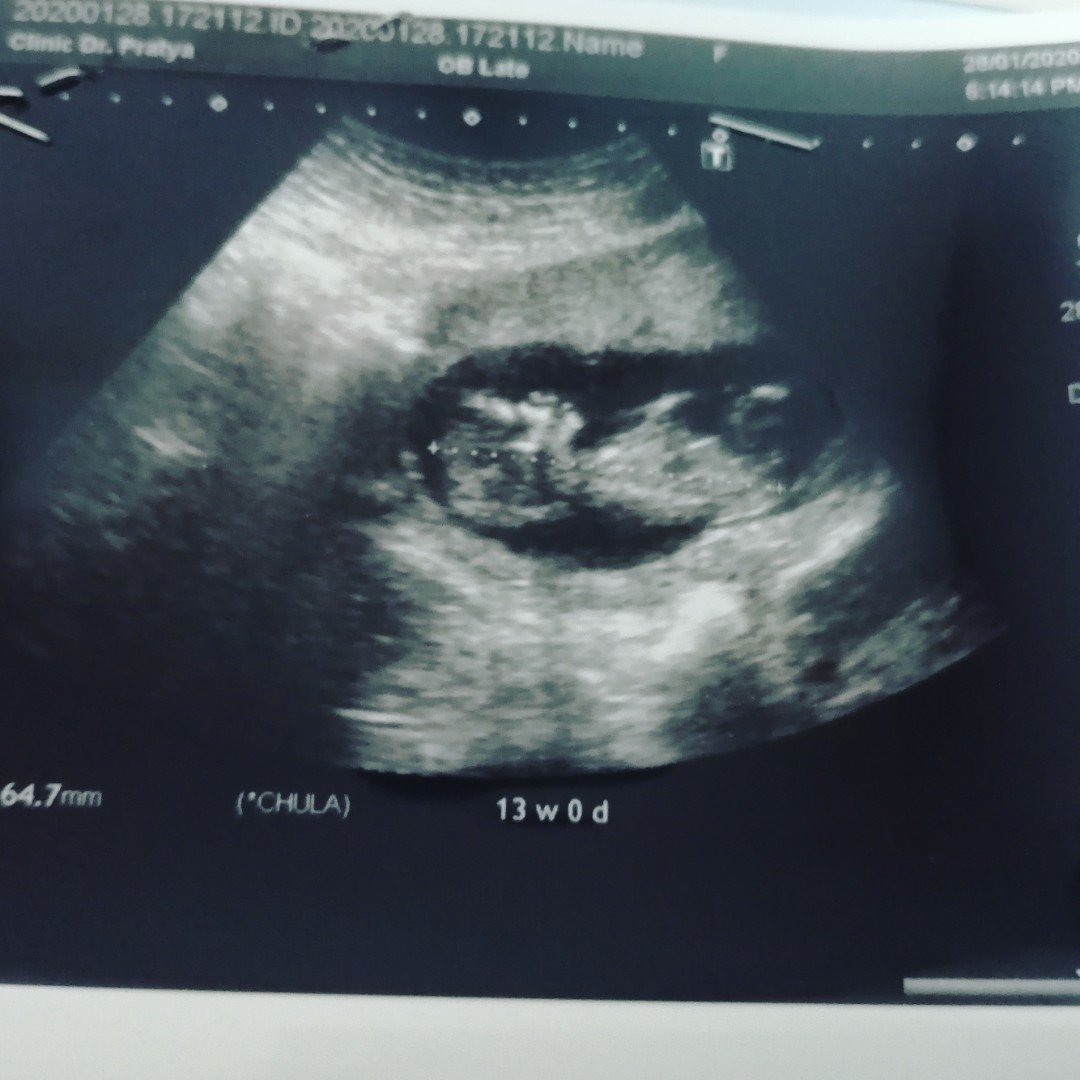

13wค่ะ

Post reply image